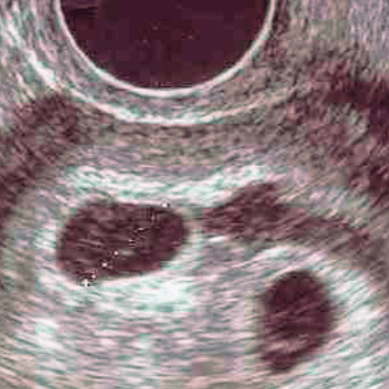

Hej :) ja miałam om 29.08 to będziemy na tym samym etapie :) 19.10 mam zamiar wybrać się na pierwsze usg :)

Ja również 19 wybieram się na usg na 15 jestem umówiona a ostatnia @podobnie jak u Ciebie bo 28.08

jA wizyte mam w sobote już tutptam nóżkami by isc. według kalkulatora apki w komórce moja kizia mizia ma 6tc 2 dni i niby mierzy 4mm ciekawe co będzie na usg .

• 2017-10-16 10.54.52.png

2017-10-16 10.54.52.png

95 KB · Wyświetleń: 152